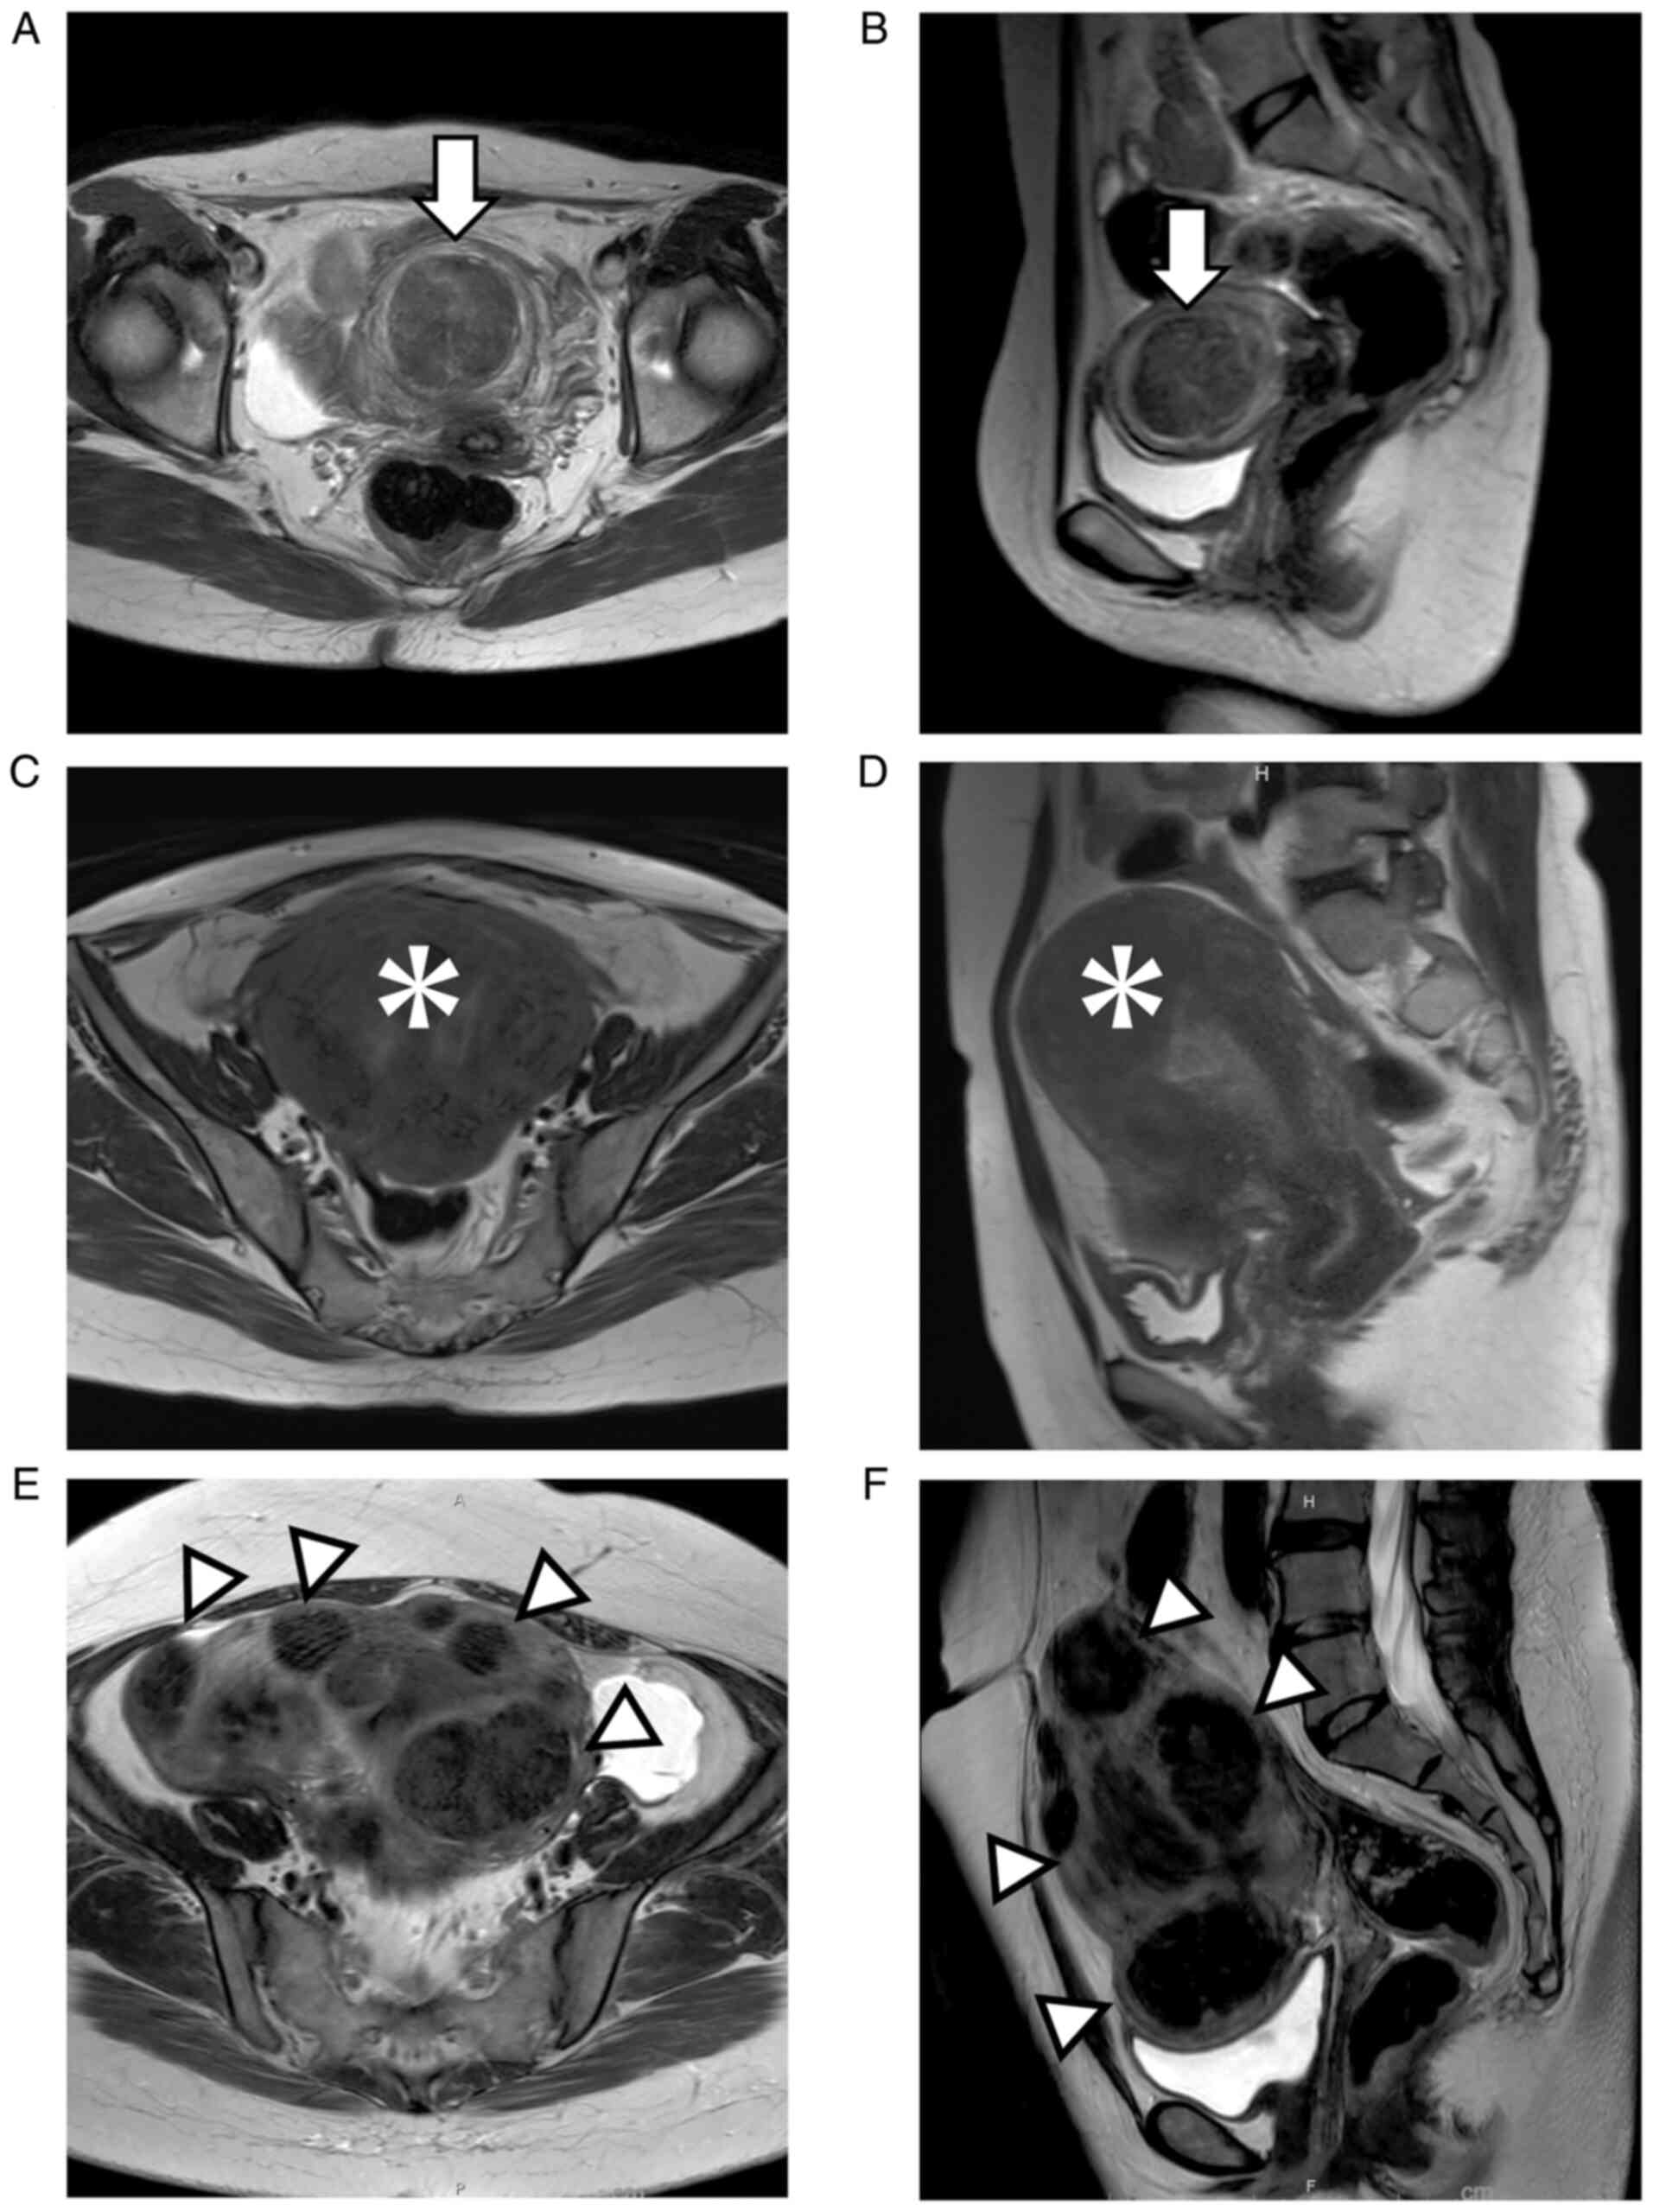

Figure 1

Clinical imaging findings: (A) axial and (B) sagittal T2-weighted MRI revealed a 5-cm uterine submucosal leiomyoma (arrows). (C) axial and (D) sagittal T2-weighted MRI confirmed multiple uterine myomas and adenomyosis (asterisks). (E) axial and (F) sagittal T2-weighted MRI revealed multiple uterine myomas (arrow heads) with a maximum diameter of 8.5 cm. MRI, magnetic resonance imaging.

A 34-year-old woman was transported by ambulance to the emergency department of the Department of Obstetrics and Gynecology, Faculty of Medicine, Oita University owing to a decline in consciousness level. She was unemployed, solitary and stayed at home all day. She had been experiencing excessive and prolonged menstruation for many years but had not sought medical care. Her last menstruation began 3 weeks before presentation and continued at the time of her arrival. Her Glasgow Coma Scale score (10) was E3V5M6. Blood testing showed a hemoglobin level of 1.1 g/dl. A 5-cm uterine submucosal leiomyoma was detected by pelvic magnetic resonance imaging (MRI; Fig. 1A and B). During her hospitalization, she was transfused 10 units of packed red blood cells. On day 13 of admission, she was discharged home. Her hemoglobin level on discharge was 8.7 g/dl. Even though anemia improved, her reactions were slow and hazy. Her mother reported that these symptoms persisted even before admission. Cranial computed tomography (CT) scans showed cerebral atrophy. It was speculated that the patient had some underlying diseases, but the patient was not willing for detailed examination. The patient underwent hysteroscopic myomectomy (Fig. 2A). At 1 month postoperatively, her hemoglobin level was 11.6 g/dl and there had been no relapse.

A 36-year-old woman presented with progressive dyspnea. She had a history of blood transfusions in our hospital for anemia during her last visit 5 years ago. Blood testing revealed a hemoglobin level of 1.7 g/dl. Pelvic MRI showed multiple uterine fibroids and adenomyosis (Fig. 1C and D). It was repeatedly explained to her that her condition was life threatening, but she refused to be hospitalized. We called her family to convince her and she ultimately agreed to be hospitalized. During her hospitalization, she was transfused 12 units of packed red blood cells. On admission day 6, she was discharged home. Her hemoglobin level at discharge was 12.2 g/dl. She and her husband had no desire for childbearing. Total hysterectomy was performed (Fig. 2B); at 1 month postoperatively, the hemoglobin level was 11.9 g/dl and there had been no relapse.

A 49-year-old woman with a history of heart failure was transported by ambulance to the emergency department of the Department of Obstetrics and Gynecology, Faculty of Medicine, Oita University due to abdominal pain and severe anemia. Blood testing revealed a hemoglobin level of 1.9 g/dl. Pelvic MRI showed multiple uterine fibroids with a maximum diameter of 8.5 cm (Fig. 1E and F). During her hospitalization, she was transfused 8 units of packed red blood cells and underwent treatment for heart failure. On admission day 5, she still needed oxygen and diuretics, although her hemoglobin level had improved to 5.9 g/dl. Nevertheless, the patient insisted on discharge owing to the lack of disease awareness, which might have been the cause for not seeking medical care previously. On admission day 9, she was discharged home. Her hemoglobin level at discharge was 9.2 g/dl. Total hysterectomy was performed (Fig. 2C); at 1 month postoperatively, the hemoglobin level was 11.2 g/dl and there had been no relapse.